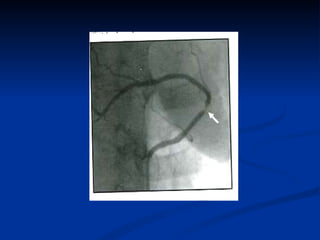

Основные инструментальные методы диагностики Ст Ст   ЭКГ ЭхоКГ Нагрузочные стресс-тесты Стресс-визуализирующие исследования КАГ Сцинтиграфия миокарда Однофотонная эмиссионная томография миокарда Компьютерная томография

Основные инструментальные методыдиагностики Ст Ст ЭКГ ЭхоКГ Нагрузочные стресс-тесты Стресс-визуализирующие исследования КАГ Сцинтиграфия миокарда Однофотонная эмиссионная томография миокарда Компьютерная томография